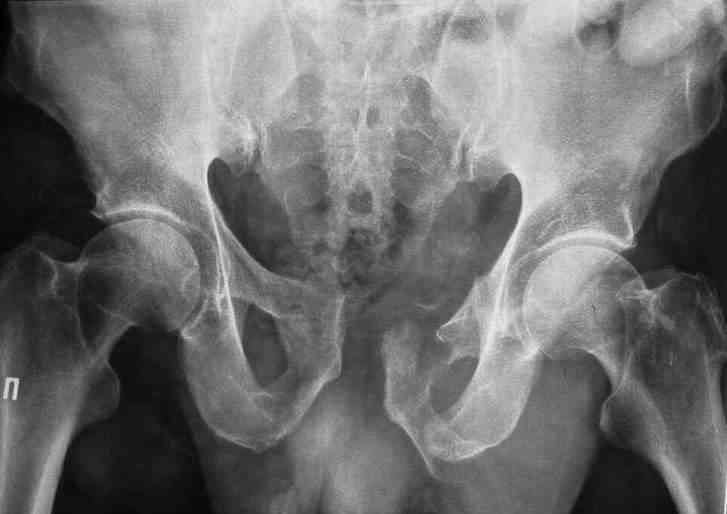

Пациент 55 лет, монтажник, травма 21.11.09 - на левое бедро обрушилась стена канавы 3м глубины.

У больного оскольчатые переломы левых лонной и седалищной костей со

смещением отломков, разрывом симфиза и распространением линии перелома

на вертлужную впадину; переломы крыла левой подвздошной кости и правой

боковой массы крестца без смещения; разрыв уретры. За последние годы